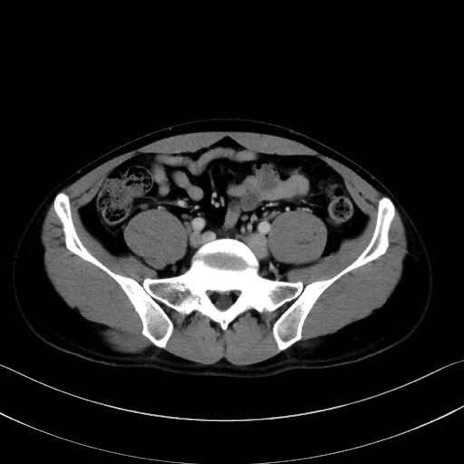

小殿筋 (Gluteus minimus)